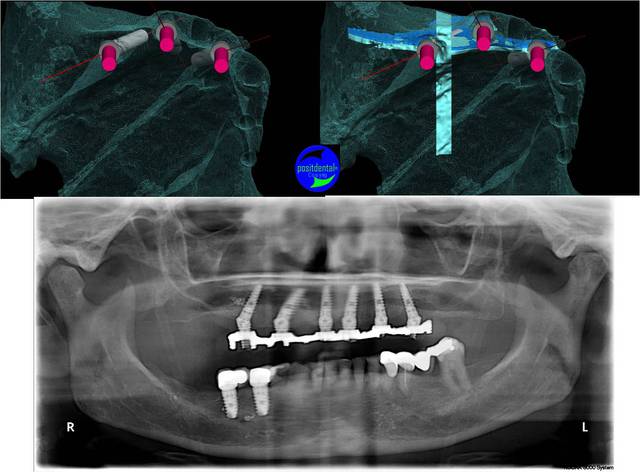

Castor la position de l’apex de l’implant angulé est aussi importante pour laisser un volume osseux pour les implants mésiaux. Sur cet exemple il était important de le placer pré de la corticale palatine vestibulaire.la densité rencontrait fait que tu n’as spécialement une corticale sur laquelle t’appuyer.

Tu peux voir que les angulations planifiées sont correctement reproduites.

un autre exemple